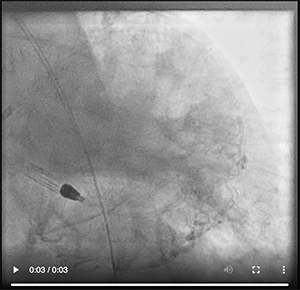

To reduce the risk of extensive stenting, the revascularization procedure would target only the LM bifurcation, while a conservative strategy was chosen for the marginal branch ostial lesion, which we believed would not further impact the patient’s prognosis. Considering the low LVEF as well as the complexity of the LM bifurcation, including the possibility of rotablator debulking of this lesion, left ventricular support was considered appropriate. An Impella CP device (Abiomed, Inc.) was implanted after careful angiographic evaluation of the right femoral and iliac arteries (Video 2).

PCI was performed via the right radial artery. Simple balloon dilatation was used to test the resistance of this calcified lesion. The nearly 360° of calcific stenosis in the ostial LAD did not yield on high-pressure dilatation. Therefore, the decision to use rotablation became definitive.

Video 2. Rotablator atherectomy fol­lowing placement of the Impella device and tentative balloon dilatation.

Video 3. Result after rotablation.